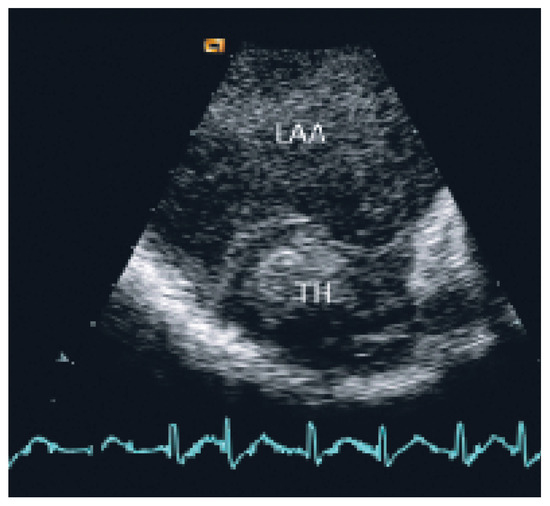

Coronary and Peripheral Thromboembolism from a Giant Left Atrium

by Marcello Di Valentino, Andrea Menafoglio, Ludwig von Segesser, Jeanne-Marie Segatto and Augusto Gallino

Cardiovasc. Med. 2006, 9(1), 28; https://doi.org/10.4414/cvm.2006.01144 - 27 Jan 2006

We report the case of a patient with a history of mitral valve replacement and a giant left atrium with acute transmural anterior myocardial infarction and concomitant acute occlusion of the right superficial femoral artery [...] Full article